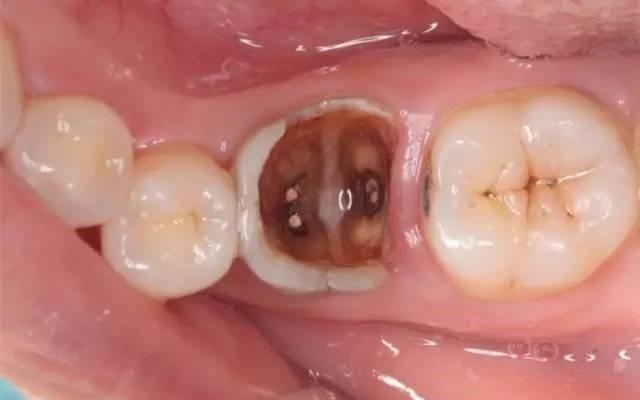

第三步深龋。

当您进食时,没法咬食物,您说:“还好,可以用另外一边牙齿咬。”牙医告诫说:“病变已经破坏到了牙本质深层,牙齿有较深的龋洞,温度刺激,化学刺激以及食物进入龋洞时引起疼痛,此时,及时做填充治疗的话还来得及保住牙髓。”